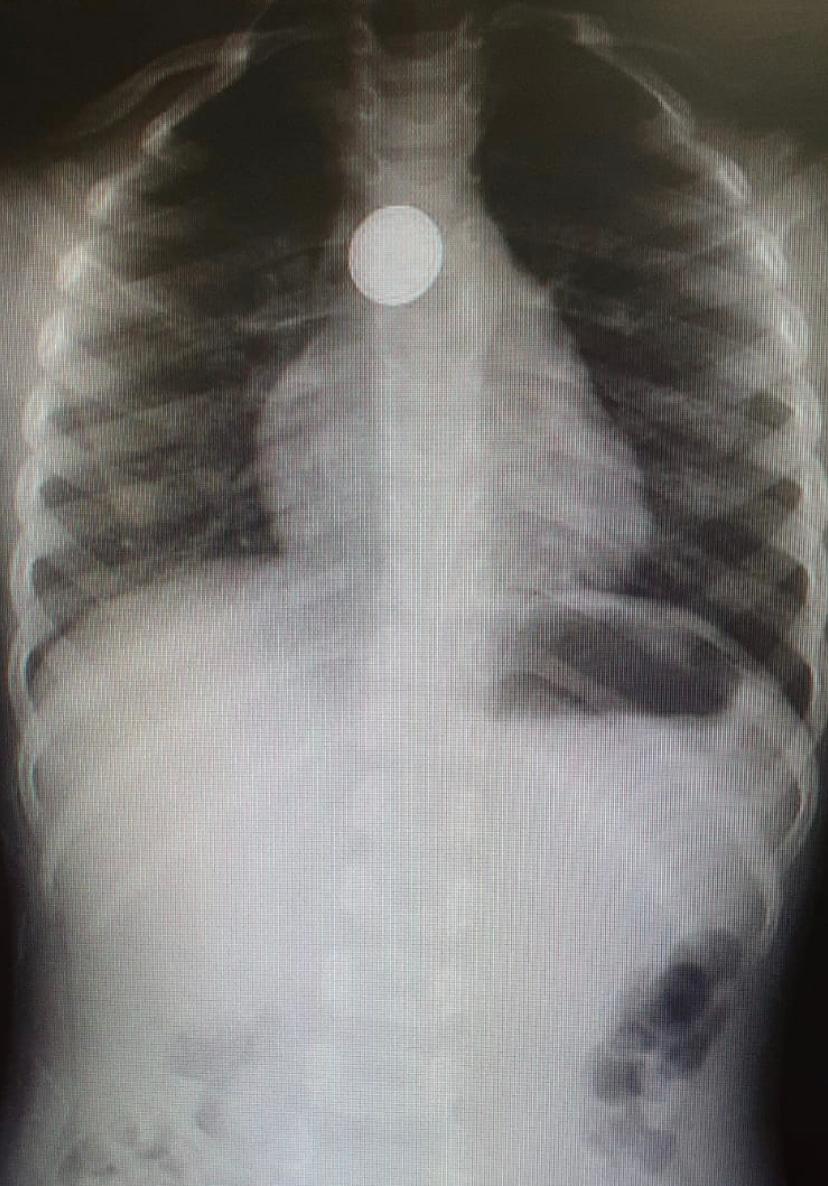

לפני כשבועיים הגיע ילד כבן 6 מיבנה למלר”ד ילדים במרכז הרפואי קפלן כשעה לאחר שבלע סוללת כפתור בקוטר 2.5 ס”מ של שלט טלוויזיה עם תלונות של כאבים בחזה. צוות חדר המיון ביצע מידית צילום חזה ובו נצפתה סוללה תקועה בחלק העליון של הושט. צוות מכון גסטרו ילדים בביה”ח, בניהולה של ד”ר מיכל קורי, ביצע בדחיפות … המשך לקרוא ילד בן 6 בלע סוללה של שלט טלוויזיה